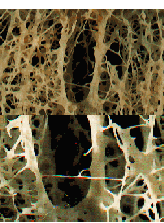

6. La imagen que se muestra a continuación corresponde a la enfermedad conocida como:

Osteoporosis